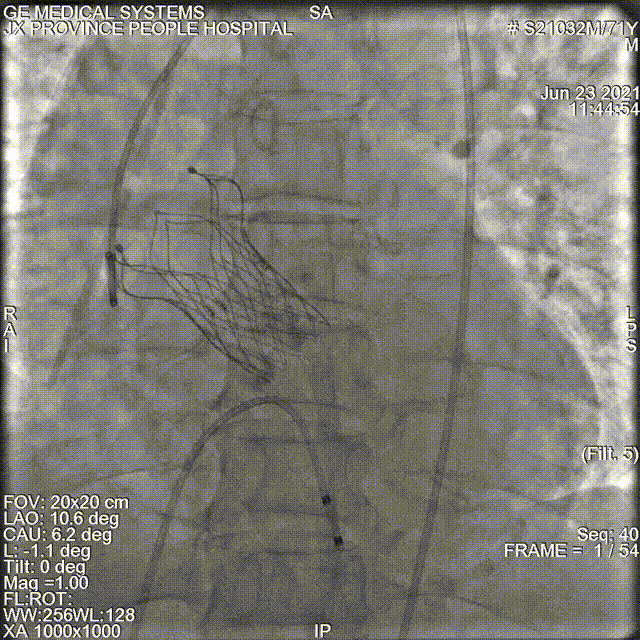

24型号VitaFlow瓣膜精准零位释放,

锚定位置良好。

此时造影显示偏少量偏中量反流,瓣膜形态欠佳,

考虑为瓣叶钙化过重,选择进行球囊后扩。

20mm球囊进行后扩

最终造影显示瓣膜仅微量反流

术后即刻超声良好:平均压差:8.0mmHg ;微量瓣周返流。